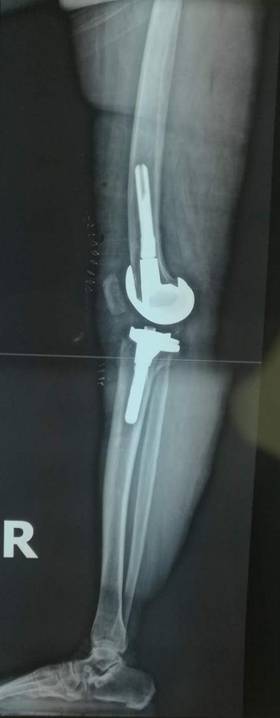

全膝表面置换术治疗重度骨关节病

优点:疗效可靠,膝关节病的最终解决方案。

术前术后对比

全膝关节翻修术